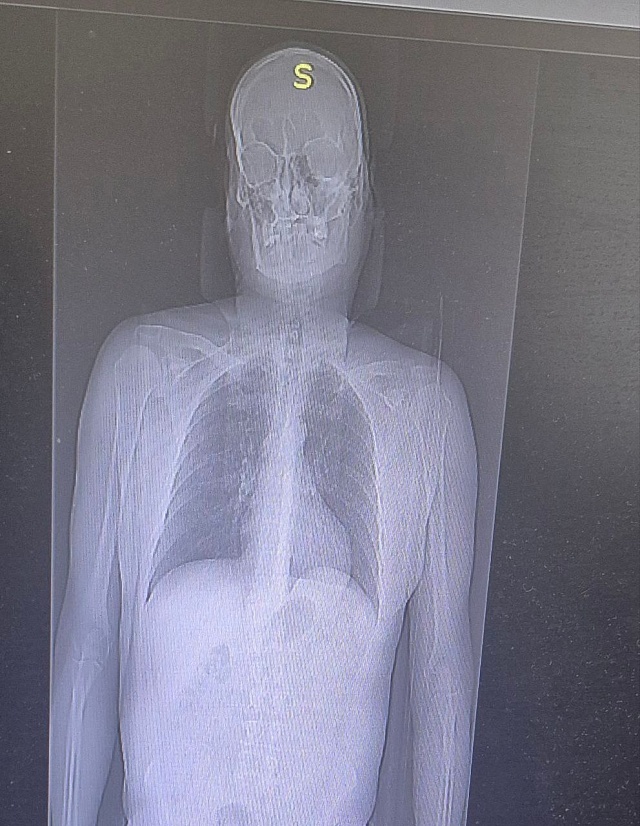

По результатам обследований у мужчины диагностировали переломы двух ребер и ушибы мягких тканей. Благодаря быстрой диагностике, грамотному обезболиванию и профессиональной помощи состояние пациента стабилизировали. Уже на следующей неделе он будет готовиться к выписке.